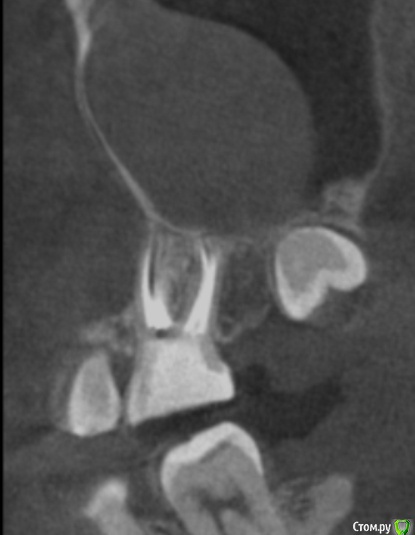

tineola Опубликовано 15 марта, 2017 Автор Поделиться Опубликовано 15 марта, 2017 (изменено) Сделала несколько скриншотов, прикрепляю к сообщению. Надеюсь, это то, что нужно.Может у кого-то из врачей будет время и возможность посмотреть КТ (ссылка в первом сообщении поста). Получила результаты гистологии первой кисты пазухи, которая год назад была удалена:Микроописание: Присланный материал представлен фрагментом полипозно-отечной слизистой оболочки, с концевым отделами слизисто-серозных желез. Эпителий слущен, гиалиоз базальных мембран, строма резко отечна, с диффузной лимфоцитарно-лейкоцитарной инфильтрацией. Патзаключение: хронический воспалительный процесс. Изменено 15 марта, 2017 пользователем tineola Ссылка на комментарий

tineola Опубликовано 15 марта, 2017 Автор Поделиться Опубликовано 15 марта, 2017 Еще скриншоты. Другая проекция из КТ. Ссылка на комментарий